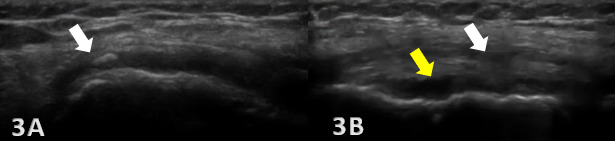

Ultrasound Technique and Diagnostic Criteria for MCL Injuries

MSK-US is highly effective in identifying the presence and severity of MCL injuries. The ligament’s superficial location makes it readily accessible for US examination, which can be enhanced with high-frequency linear transducers to produce detailed soft-tissue images. Dynamic imaging during knee flexion and extension, not possible with MRI, further improves the diagnostic accuracy of US by demonstrating the static functional integrity of the MCL. The examination involves scanning in both longitudinal and transverse orientations, assessing the ligament for echotexture, continuity, and any associated anechoic (fluid) collections indicating acute injury. Diagnostic criteria for MCL injuries are based on ligament thickness, loss of the normal fibrillar pattern, and the presence of preligamentous fluid. One tip when assessing the femoral insertion of the superficial fibers of the MCL is gently tilt the probe along the MCL curved course to avoid the anisotropic effect of a false hypoechogenicity.18